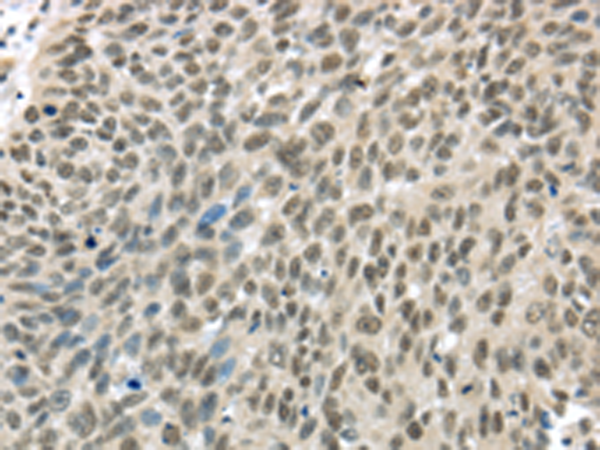

分类: 科研抗体货号: P08918别名: Ptg-2; TSC22; TGFB1I4应用: IHC反应种属: Human, Rat